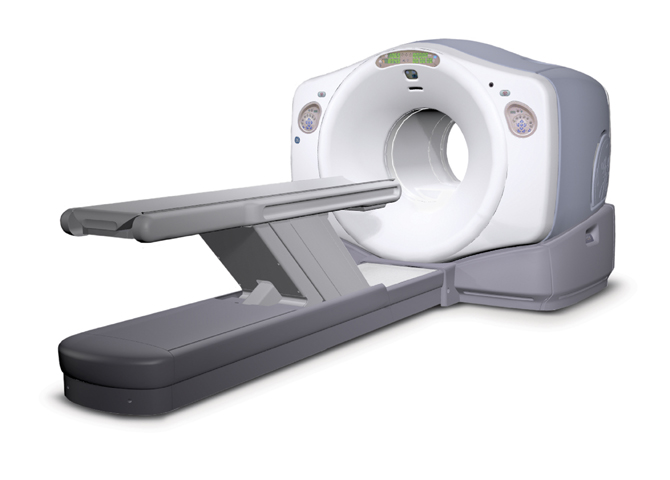

Početkom 2009. dostavili smo informaciju KBC-u Rijeka odgovor na upit o projektu javno-privatnog partnerstva utemeljenu na projektu dogovorenom i do tada provedenom u KBC „Sestre milosrdnice“ i KBC Split između bivšeg ministra zdravstva i socijalne skrbi Nevena Ljubičića te Poliklinike Medikol iz 2007., no KBC Rijeka tim dopisom nije tražio nabavu PET/CT uređaja niti je HZZO odbio takvu nabavu, priopćio je Hrvatski zavod za zdravstveno osiguranje (HZZO).

HZZO ističe kako sukladno zakonskim odredbama nema ingerencije u procesu nabave medicinske opreme pa tako niti PET/CT uređaja te podsjeća kako bolnice zahtjeve podnose Ministarstvu zdravstva i socijalne skrbi.

Neovisno o informaciji koju je HZZO uputio bolnicama, svaka je od njih u obvezi provesti postupak javne nabave, čime se u potpuno ravnopravan položaj stavljaju svi potencijalni ponuditelji PET/CT uređaja. (Hina)